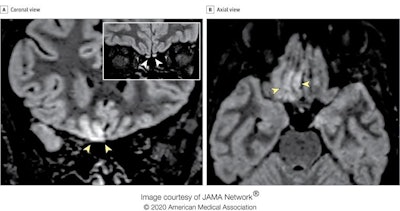

MRI scans of a 25-year-old Italian radiologic technologist who contracted COVID-19 and lost her sense of smell suggest the virus may invade the brain through the olfactory pathway and cause dysfunction of sensorineural origin. This finding was published online by JAMA Neurology on May 29.

"To our knowledge, this is the first report of in vivo human brain involvement in a patient with COVID-19 showing a signal alteration compatible with viral brain invasion in a cortical region (i.e., posterior gyrus rectus) that is associated with olfaction," noted Dr. Letterio Politi and colleagues from the department of neuroradiology at the Scientific Institute for Research, Hospitalization, and Health Care (IRCCS) Humanitas Research Center, Milan. "Alternative diagnoses (e.g., status epilepticus, posterior reversible encephalopathy syndrome-like alterations, other viral infections, and anti-N-methyl-D-aspartate receptor encephalitis) are unlikely given the clinical context."

The researchers performed two MRI exams on a 1.5-tesla scanner using a 20-channel phased-array head/neck coil. They used no contrast agent and acquired 2D and 3D FLAIR, T2-weighted turbo spin-echo, T1-weighted spin-echo, and high-resolution diffusion-weighted images. Constructive interference in steady-state and susceptibility-weighted imaging sequences were also employed.

In follow-up MRI performed 28 days later, the signal alteration in the cortex had completely disappeared and the olfactory bulbs were thinner and slightly less hyperintense. The patient had recovered from anosmia. On May 6, a blood sample was positive for the immunoglobulin G antibodies against the SARS-CoV-2 virus.